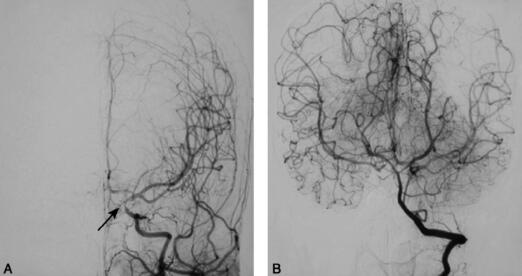

全脑DSA(外院2010年9月20日):双侧颈内动脉纤细,右侧颈内动脉床突上段闭塞,左侧颈内动脉床突上段狭窄,双侧大脑前动脉和大脑中动脉由基底动脉经后交通动脉代偿供血,左侧大脑后动脉起始段狭窄(图3)。

图3 全脑DSA(2010年9月20日):A.显示左侧颈内动脉床突上段狭窄(箭头);B.双侧大脑中动脉及大脑前动脉由基底动脉经后交通动脉供血